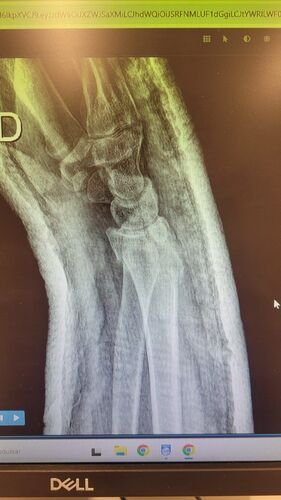

Meu nome e Isabella, mais conhecida como Snow, eu estava andando de muleta e a borracha dela saiu e eu tenho problema de equilibrio devido ao meu femur, bati o osso e piorou a situação, tive o radio do braço afetado e colocaram pino e deram um jeito de reverter porque eu ficaria com movimento do braço e mão comprometidos, tive traumatismo craniano porque bati a cabeça, esse ano eu já tinha sofrido um depois de um aparelho de raio x cair na testa mas fiquei sem sequelas na cabeça. Bom como muitos que me acompanham eu tenho uma condição rara entre mulheres que eu tenho os ossos do fêmur necrosados em mais de 75% desde 2022, eu sofri um acidente hoje andando de muleta, machuquei o fêmur, rosto, tivd que operar porque era uma emergência, não tenho muitas fotos pois estava internada mas tentei no SUS e não tinha pino de titânio,meu caso era de extrema urgência, eu to vendendo tudo e abrindo mão ate do meu apartamento pra cobrir a cirurgia e tenho ate final de setembro pra bater pelo menos 20 mil de meta, tenho inúmeras vakinhaa mostrando minha real doença autoimune e uma delas sendo rara que é osteonecrose bilateral do fêmur, o tratamento tá sendo todo particular mesmo sendo paciente do hospital das clínicas, ainda e difícil e nem sempre consigo as coisas, eu tento de todas formas é isso ainda pode me prejudicar na minha carreira, detesto pedir ajuda mas não tenho opção, a comunidade da minha área entre outros interesses sempre me apoiaram e infelizmente veio com humildade e de cabeça baixa pedir ajuda, faz tempo que tento recomeçar minha carreira desde o diagnóstico e nunca desisti dos meus sonhos e cirurgia

Vou deixar imagem atual do acidente abaixo e de algumas vakinhas anteriores